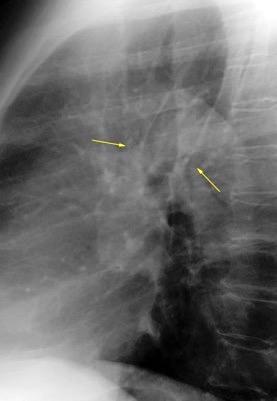

Líneas paraespinales formando un “paréntesis” por encima del diafragma. El signo señala el origen “intratorácico” de la lesión.

Conrad A et al. Pott’s disease associated with large and multiple abscesses in a 30-year-old migrant from Chad. BMJ Case Rep 2018

(lesiones toracoabdominales) La divergencia de las líneas paraespinales apunta a lesión toracoabdominal, que desde el tórax desciende y penetra en el abdomen.

Signo del “iceberg” positivo en Tb vertebral

Afectación por vía hematógena. Región dorsolumbar más frecuente. Afectación inicial: irregularidad de los platillos vertebrales, disminución del disco intervertebral con esclerosis ósea adyacente. Kim. Radiographics.2001